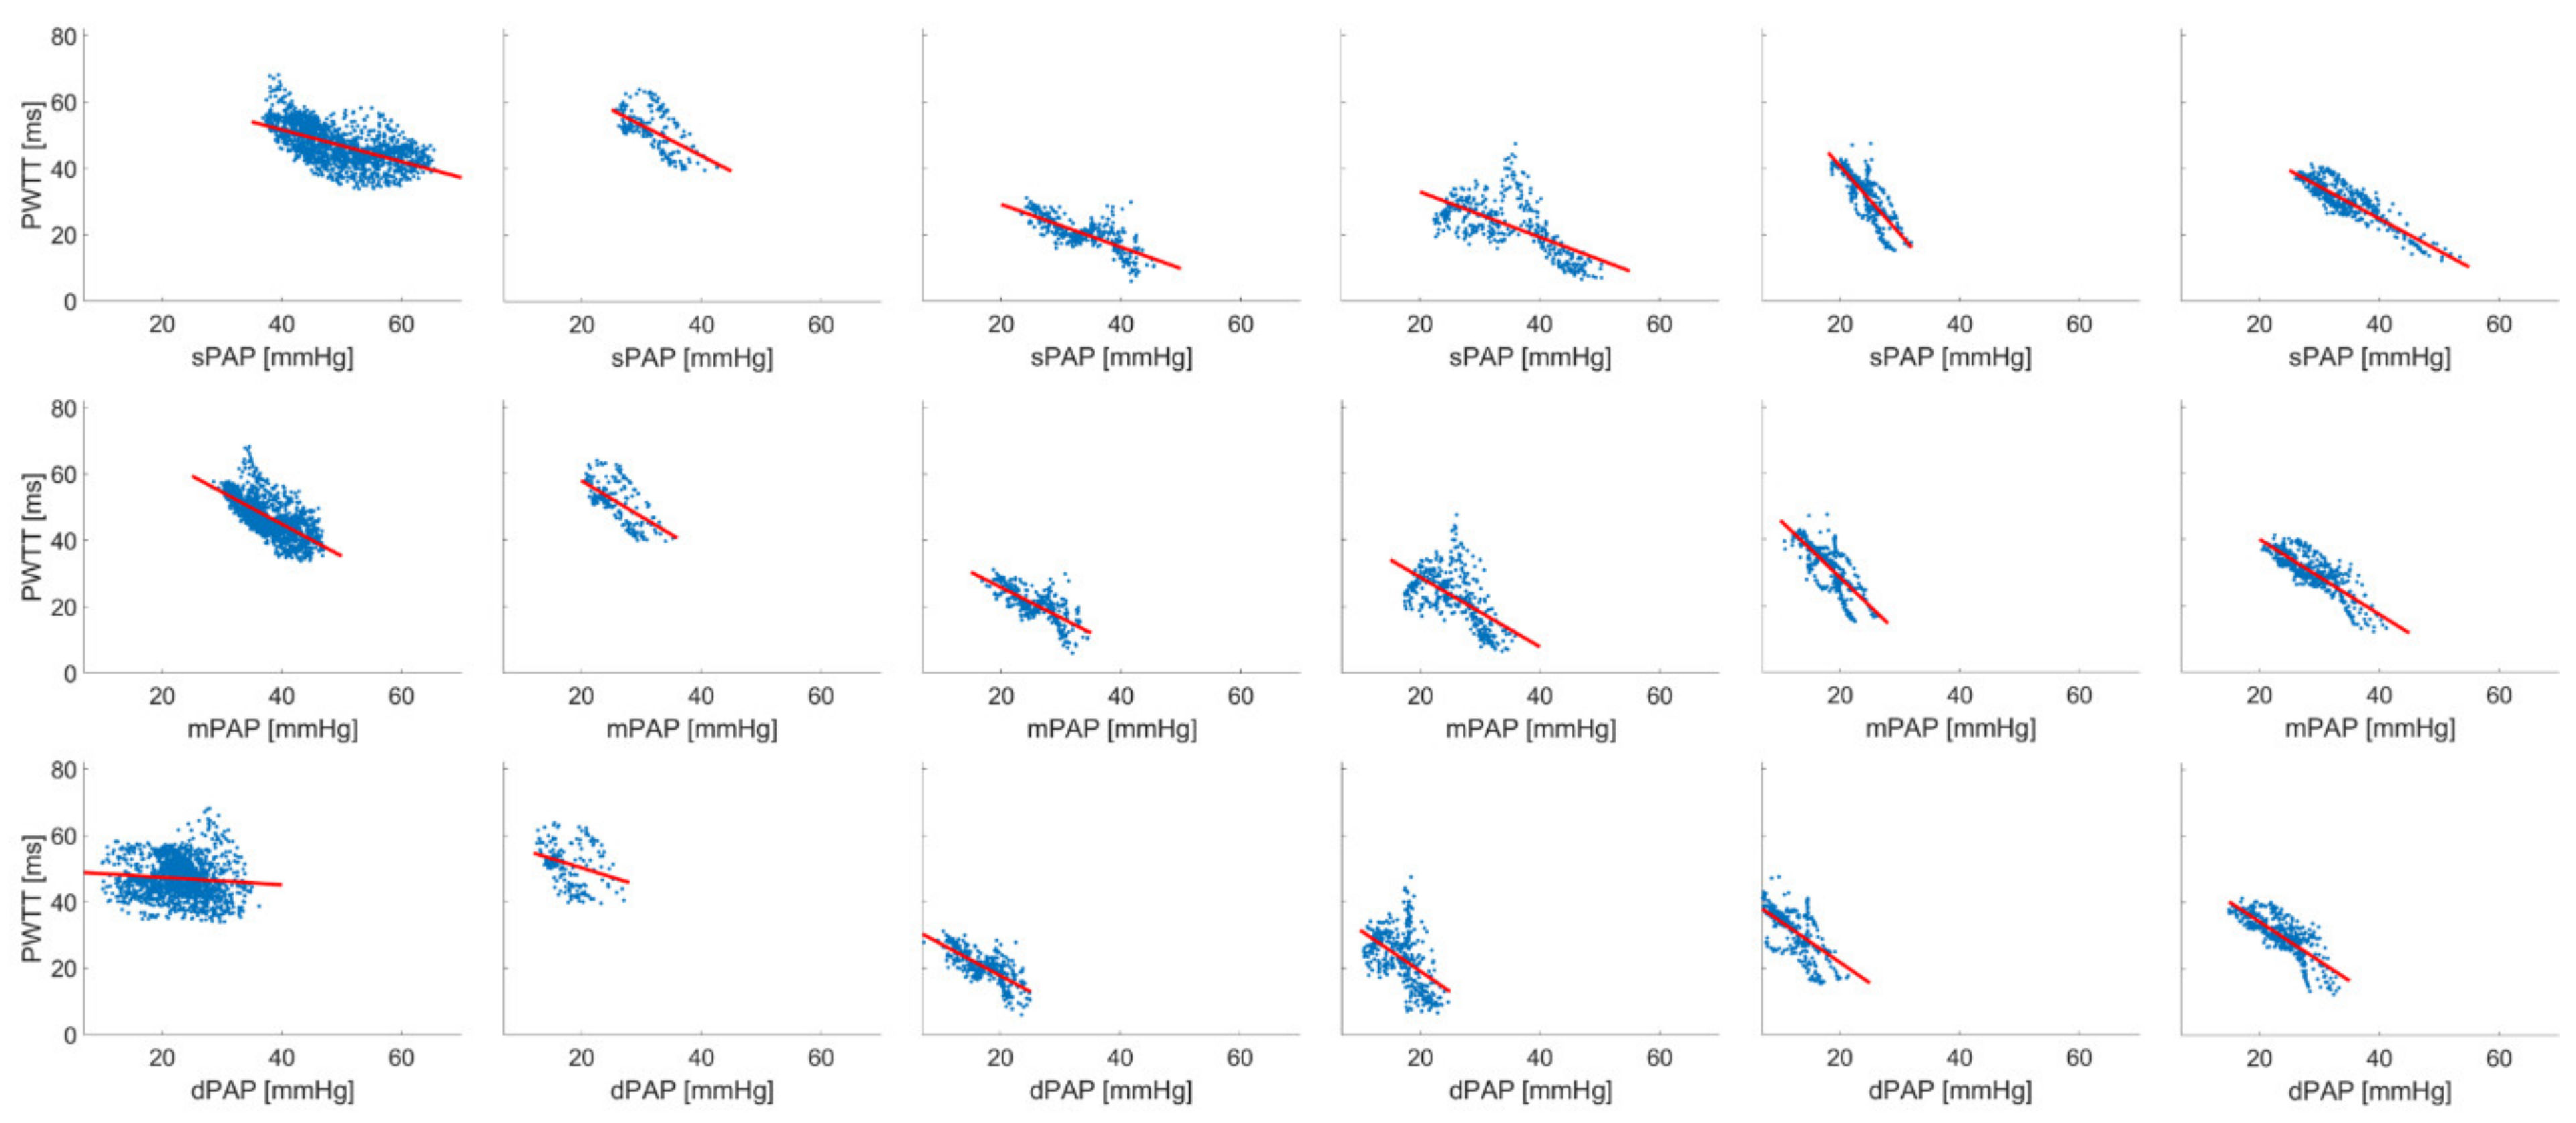

3. Results

4. Discussion